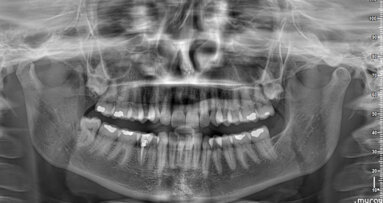

A dental panoramic tomogram was obtained, and a high-density area was observed at the apical level in the area of tooth #21. A 3-D computed tomography (CT) scan was then obtained, and it showed the presence of a supernumerary tooth in the periapical region of tooth #21, palatally located and oriented upwards. Necrosis by compression of the neurovascular pedicle of tooth #21 due to the expansion of the erupting follicle of the supernumerary tooth was diagnosed.

When she presented to the endodontist, the tooth had darkened to a grey-brown colour. In addition to that, the tooth no longer responded to pulp vitality tests. During the visit, the endodontist performed periapical radiographs of the area (Fig. 2), and based on this the existence of a supernumerary tooth at the apical level of the incisor growing towards the floor of the nasal cavity was confirmed. The endodontist requested a CT scan to study the position and assess the possibility of surgical extraction.